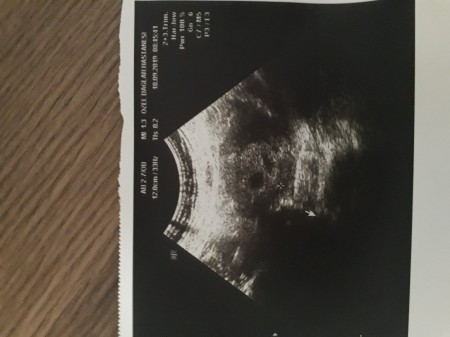

Tüp bebekte boş kese olur mu. Tüp bebekte yaşanan boş gebelik durumuna su gebeliği ismi de verilmektedir. Hakkında merak ettikleriniz güvenilir cevaplarla. Tüp bebekte boş gebelik durumunun tanısı ultrasonda kalp damarları ile embriyonun görülmesi gerekli olan haftalarda görülmemesi ve boş izlenmesi. Boş gebelik ile çok erken dönemdeki normal bir gebeliği ayırdetmenin en önemli yolu kese içinde yolk kesesi adı verilen yapının izlenmesidir.

Tüp bebekte kimyasal ve boş gebelik. 5 boş gebelik nasıl sonlandırılır. öte yandan kesenin ultrasondaki görüntüsü de bu iki durumun ayrımında yol gösterici olabilir. Normal hayatta da bunlar olur tüp bebekte de olur yani anne rahmine embriyo tutunur orada bir plesenta alanı oluşturur orada beta hcg salgılamaya başlar fakat bir miktar sonra devam etmez gebelik o zaman o biyokimyasal gebeliktir.

Gebeliğin kese kısmını oluşturan zar ile plasenta oluşurken yapıların iç kısmında bebek bulunmaz. Boş gebelikler bir kez olur ve çok az bir grupta birden çok tekrarlar. 2 veya 3 defa düşük geçmişi olmadan özel kan ve genetik tahlilleri yaptırmaya ihtiyaç duyulmaz.